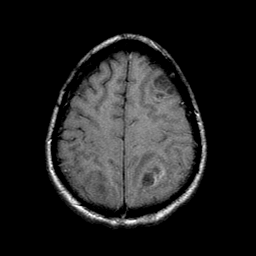

Sarcoma, MR Study #1 mr-t1 -- Slice #19

[Home][Help][Clinical] Slice 19